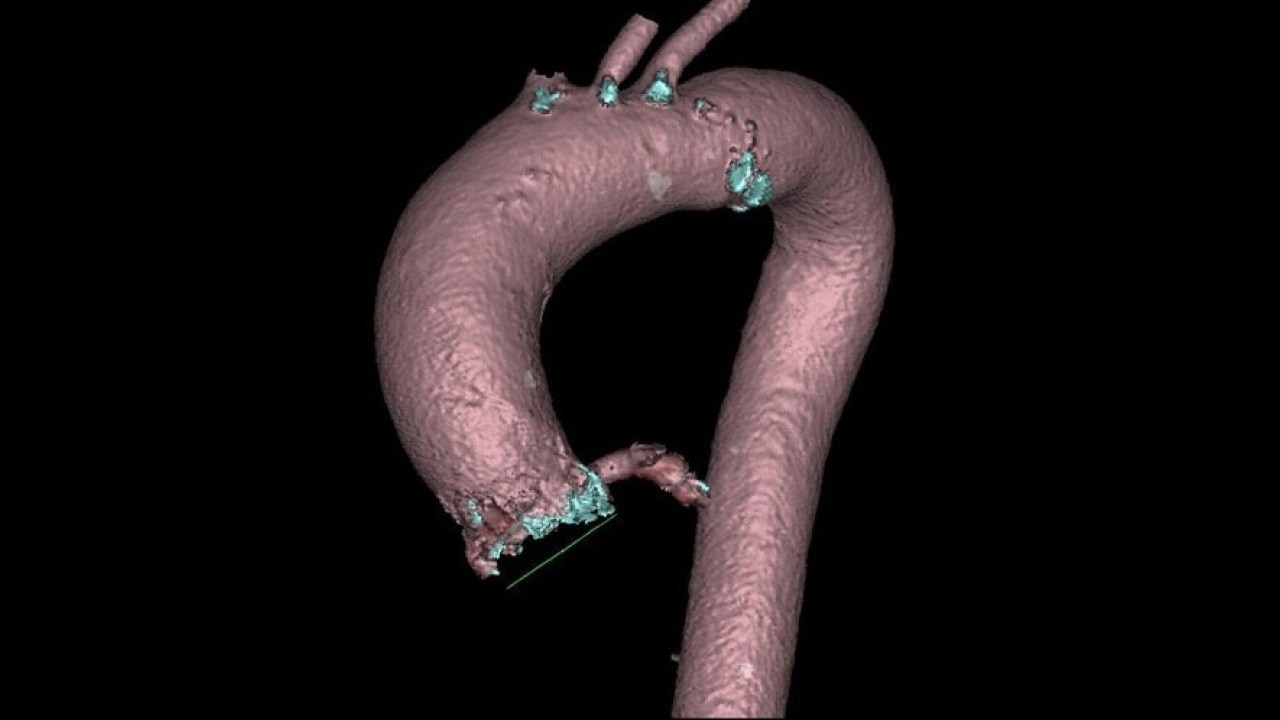

The Valve Planning protocol in the VesselIQ Xpress application lets you visualize cardiac anatomy with the degree of detail required to evaluate the presentation of the aortic valve. Armed with this information, you can develop a pre-procedural TAVR/TAVI plan to establish a therapy strategy for the patient.